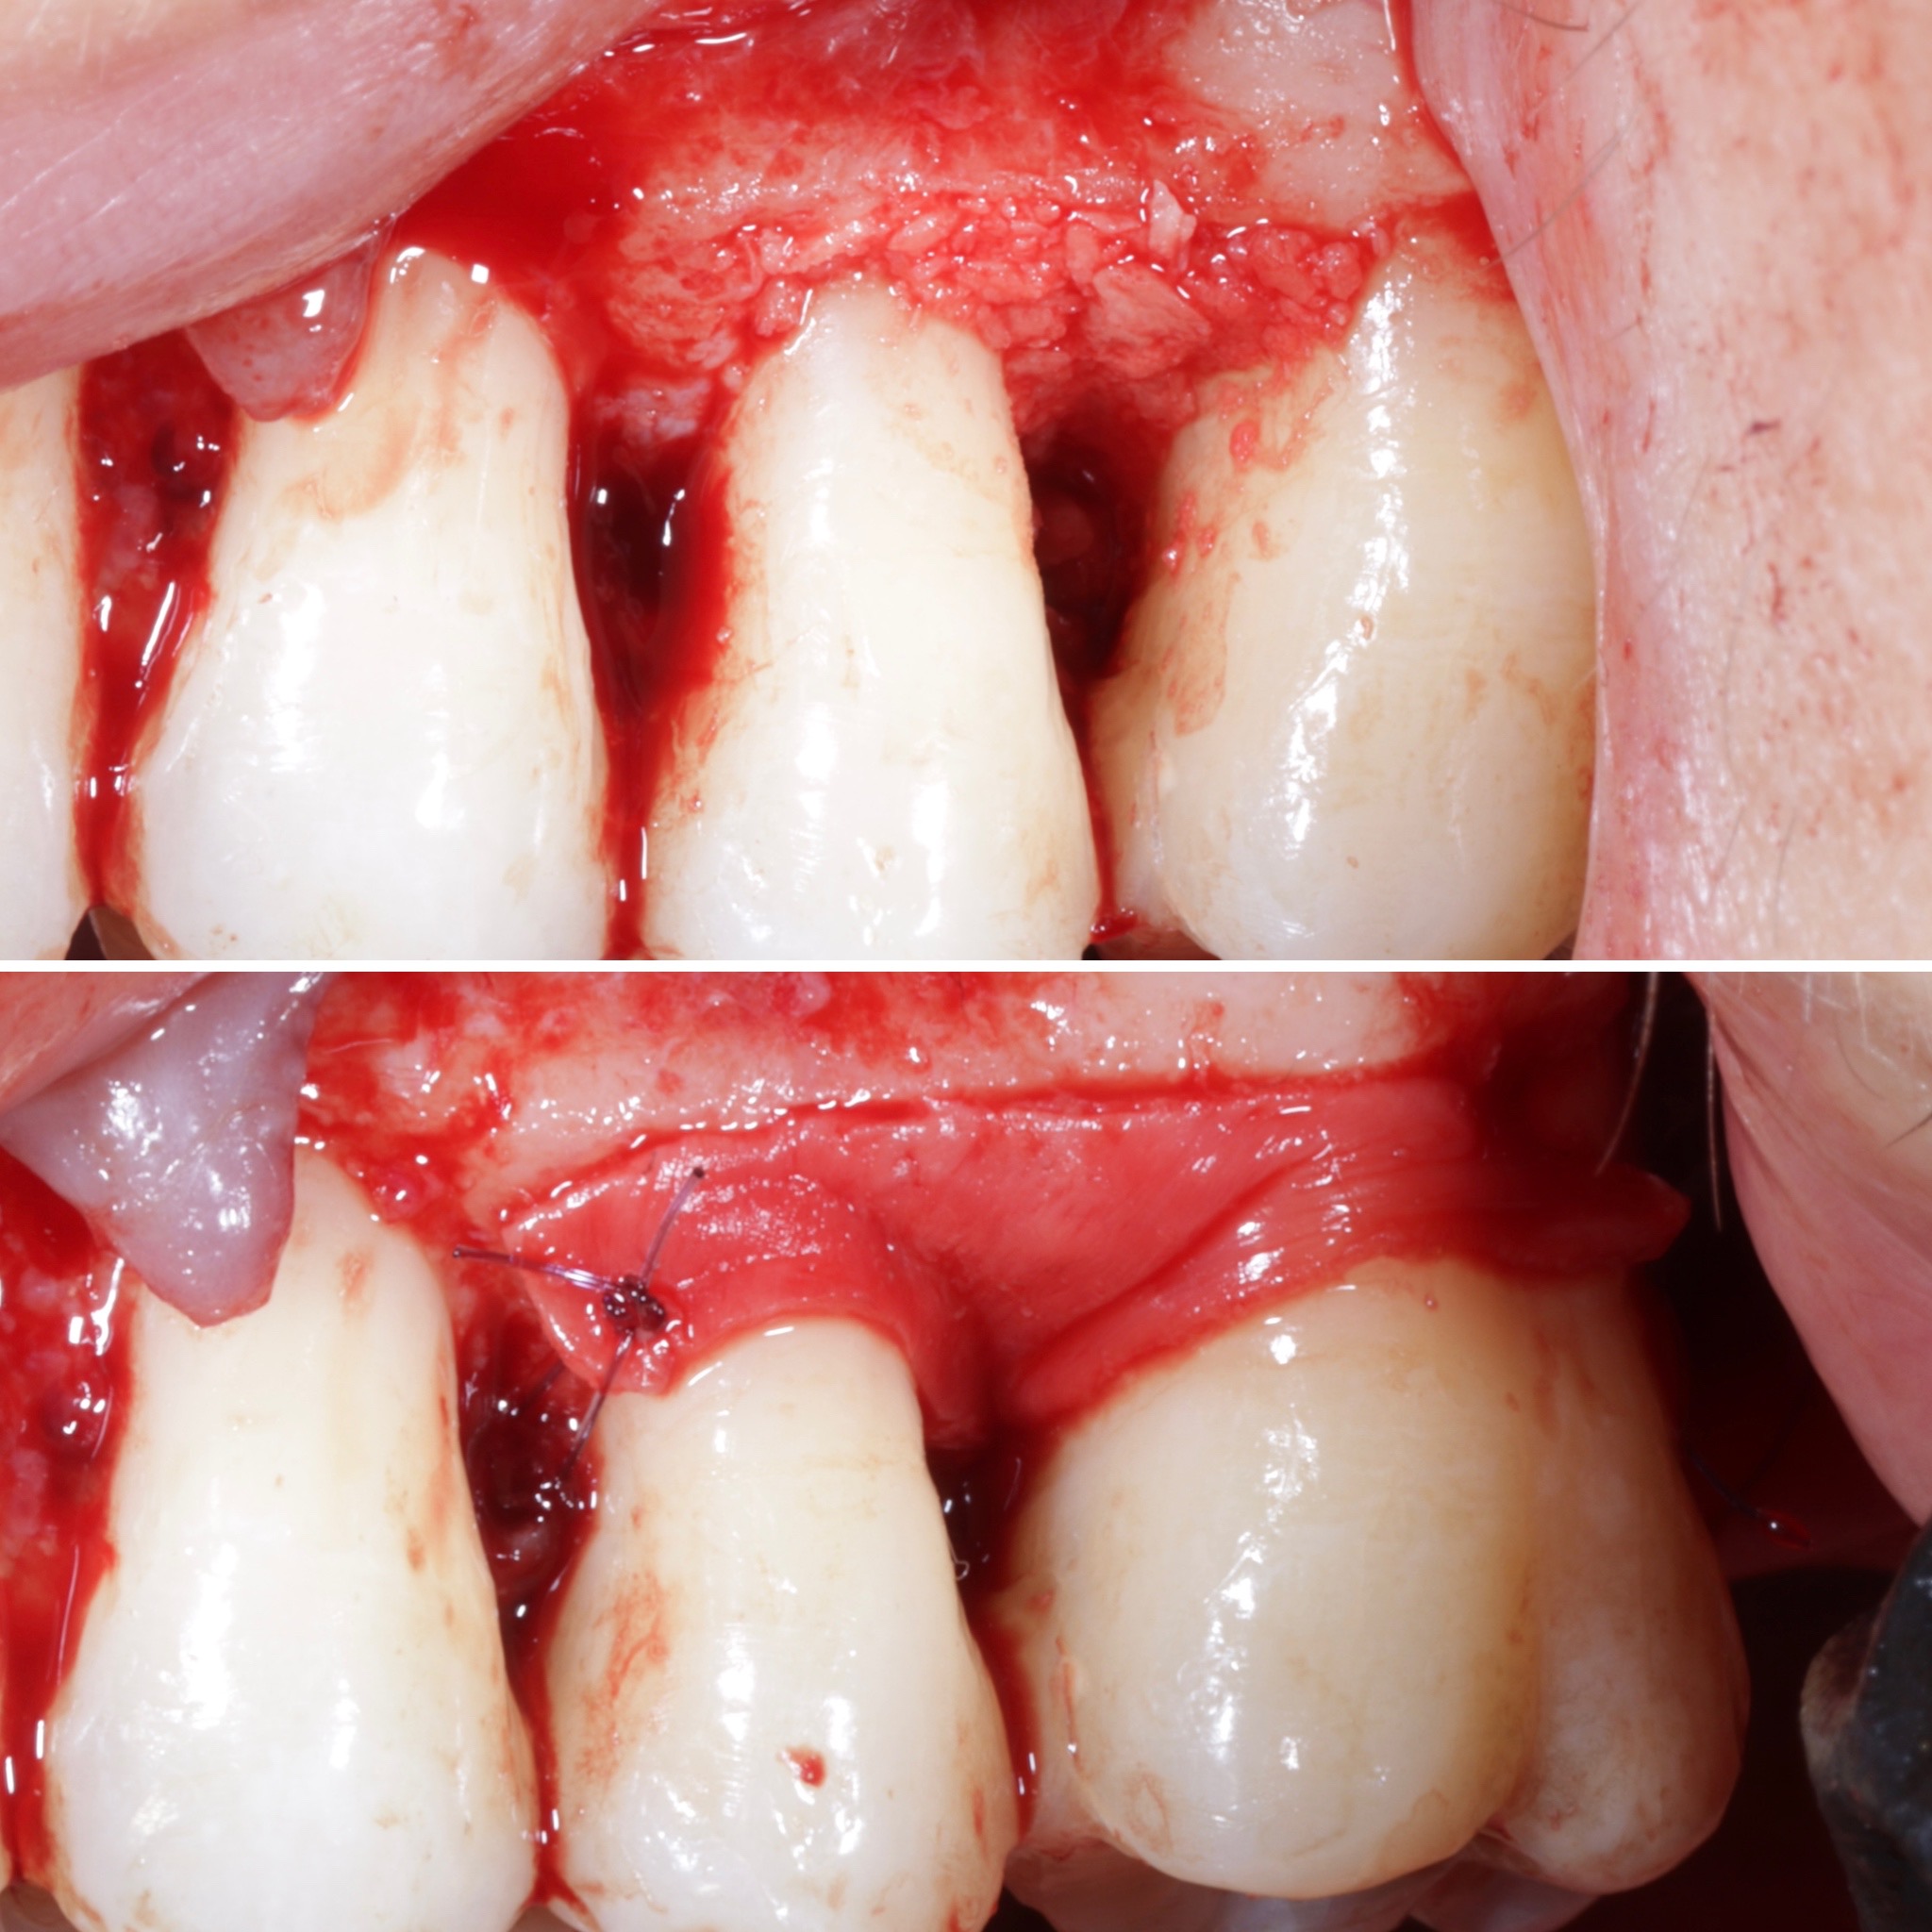

Durante una mañana, asistirás a una Cirugía Mucogingival de recubrimiento radicular de recesiones múltiples en IV y V sextante (36 a 43).

Gracias al uso del microscopio y a la proyección en tiempo real en pantalla, verás exactamente lo mismo que veo yo durante la cirugía, sin tener que estar

Se realizará todo el procedimiento con un microscopio operatorio, lo que permite al alumno ver toda la cirugía en directo en una pantalla en la sala de cirugía.

Aprende la planificación y técnica de la cirugía Mucogingival para el recubrimiento de recesiones y aumento de banda queratinizada en el sector anteroinferior

La formación comenzará con la presentación del caso clínico que se abordará durante el curso, seguida de una cirugía en directo, que permitirá observar paso a paso el procedimiento y la toma de decisiones clínicas. Durante la jornada se profundizará en los conceptos biológicos aplicados a

Una estancia clínica pensada para quienes quieran iniciarse o dar un paso más en el campo de la cirugía mucogingival. Durante esta experiencia tendrás la oportunidad de aprender en directo cómo se planifica y se lleva a cabo una cirugía mucogingival mediante técnica de Túnel.

La sesión